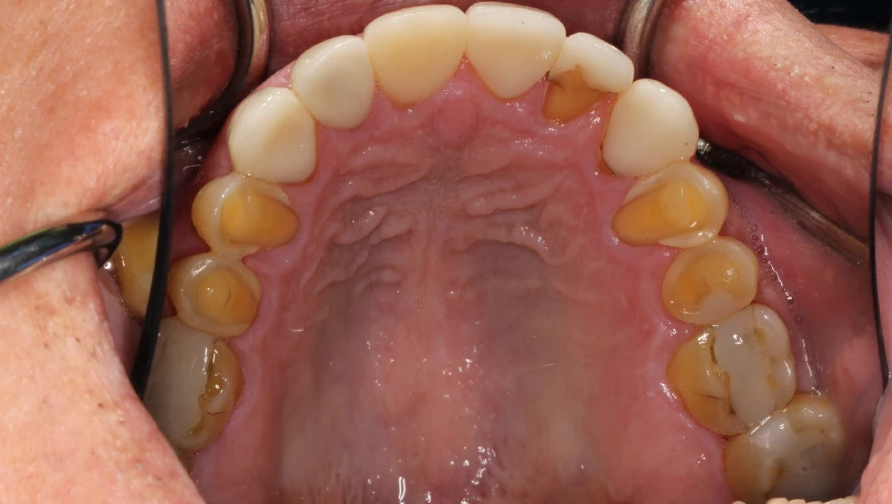

Walk through the bustling streets of Manila, from the commercial hubs of Makati to the crowded neighborhoods of Tondo, and you will see a generation of teenagers grappling with a silent health crisis. Their smiles tell a story not just of poor diet and bad habits, but of a larger system failing them. While the common dental problems are clear—cavities, gum disease, and enamel erosion—the roots of this crisis run much deeper than just forgetting to floss.

The Sugar Onslaught: Their diets are dominated by cheap, accessible sugar—from sugary milk teas and sodas to processed snacks from convenience stores. This constant sugar bath fuels acid-producing bacteria, leading to rampant tooth decay and eroded enamel, making teeth sensitive and prone to cavities.

Smoking and Vaping: The rise of vaping as a "cool" habit, alongside traditional smoking, is a disaster for oral health. These habits dry out the mouth, reducing protective saliva, and significantly increase the risk of gum disease (gingivitis), stained teeth, and in the long term, oral cancer.

As detailed by dental experts, these are the 5 Common Dental Problems and How to Prevent Them, including tooth decay, gum disease, and bad breath—all of which are directly linked to these lifestyle choices.